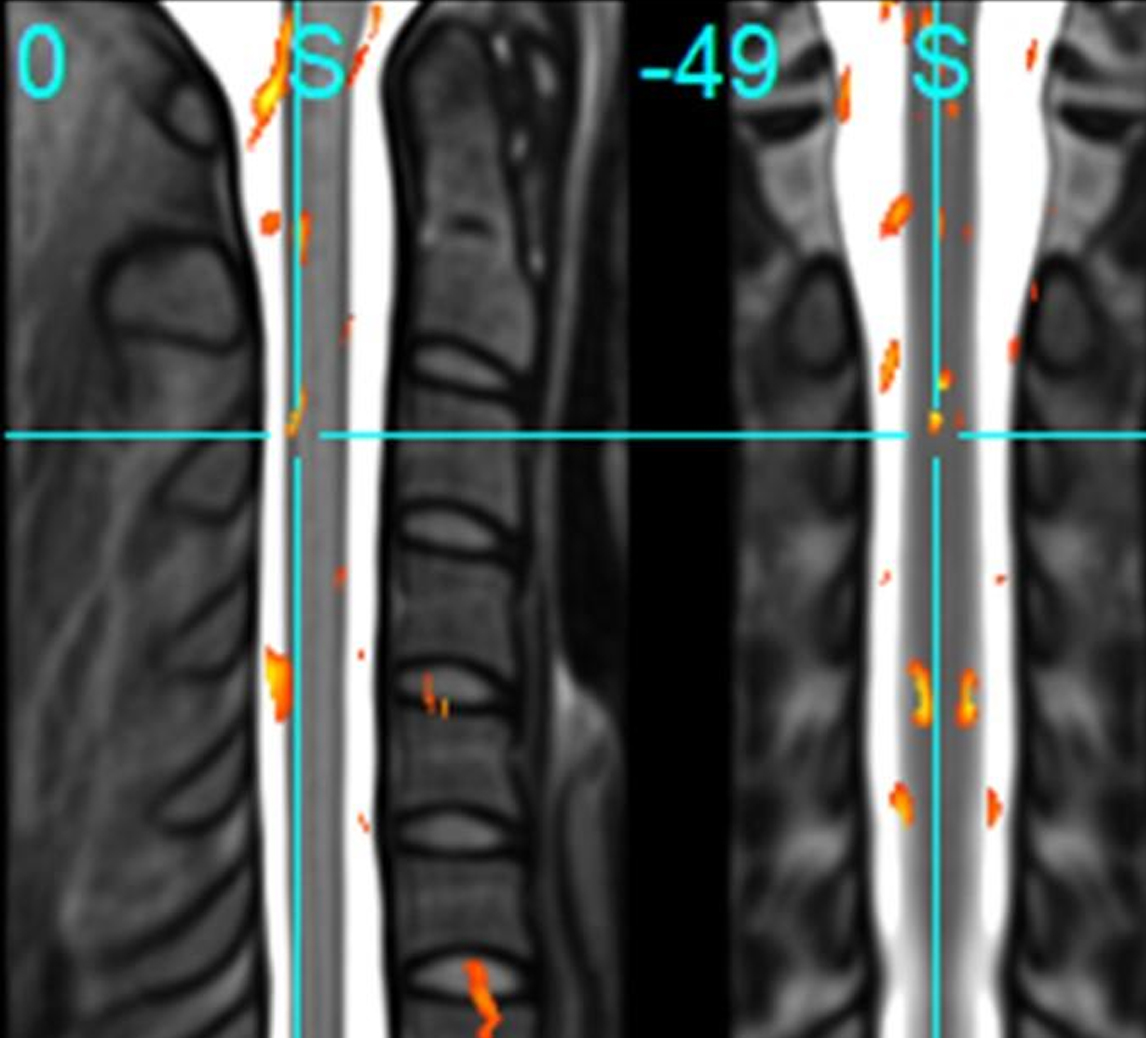

上图中橙色部分表示大脑与脊髓管神经信号活动量的差异之处。通过这种方式可以观测到人在运动时,不仅使用了大脑,还使用了脊髓。

(左侧图像为上端脖子附近的脊髓侧面图,右侧为脊髓正面图)。